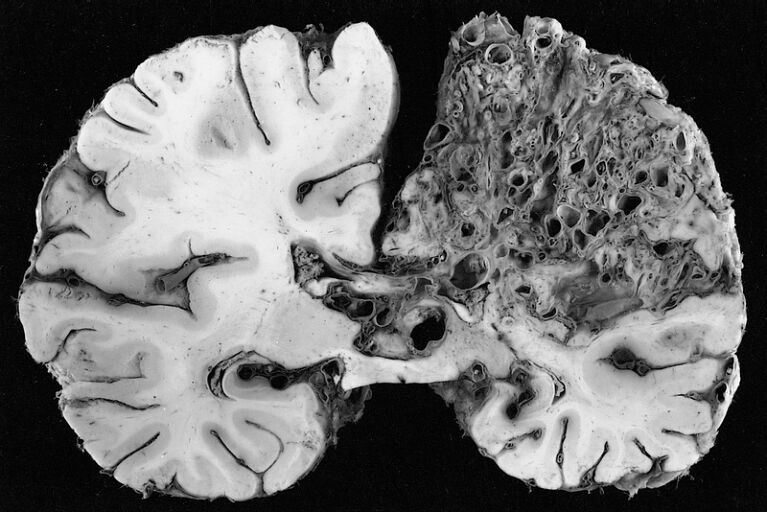

Мозги прионы

Мозги прионы 117 фото